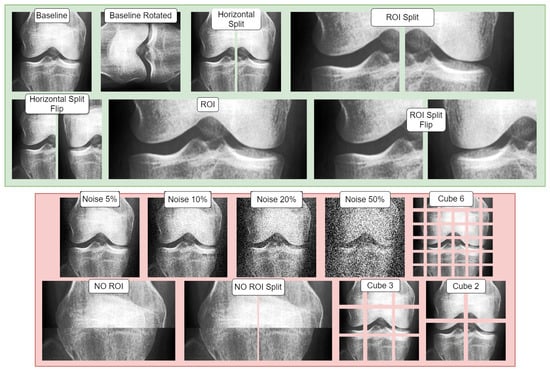

In our research, we divided our dataset into distinct splits and applied base data augmentations to each of these splits. We created two sets of base data augmentations. The term ‘base data’ refers to permanent modifications made to all the data (‘offline’) before introducing any ‘online’ affine augmentations during the training phase (Table 1). The first set of augmentations focused on positive or supportive modifications, exploring the potential benefits of incorporating image-based artificial diversity during training. The second set, conversely, involved negative/adversarial augmentations, intended to challenge the classifier. This approach aimed to help identify potential confounds in the classification task and test the model’s resilience. Table 2 showcases all the conditions used, while Figure 3 visualizes the base augmentations made. The specifics of each type of augmentation are further elaborated in the following section.

2.5.3. Adversarial (Negative) and Supportive (Positive) Augmentations Visualization

Figure 3 illustrates both adversarial and supportive/positive augmentations. In the green window, the supportive augmentations are displayed as variants of the provided baseline image. Likewise, in the red window, one can observe the adversarial variants and their visual form, all applied on the same unaltered baseline image shown in the green window.

Figure 3. Visualization of the study’s base data augmentations: red indicates negative/adversarial augmentations and green shows positive/supportive augmentations. Each transformation is demonstrated on provided baseline image.